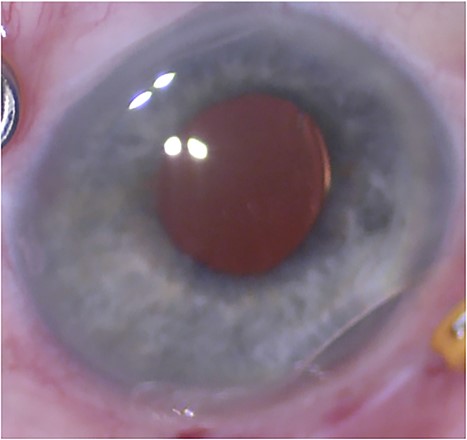

On post-operative day one, the lens optic was seen tilted (Fig. 2A) while the lens haptic were visible at the sclera superiorly and inferiorly. Intraocular pressure at this time was 6 mmHg. The patient was taken to surgery on the following week. Intraoperatively, the lens optic was found tilted nearly 90° with noticeable damage to the bilateral optic-haptic junctions (Fig. 2B) with intact haptic at orientation into the sclera on endoscopic view (Fig. 2C). The damaged lens was exchanged with an AKREOS lens fixated using 8–0 monofilament sutures as the previous case. FAX was performed once more. On post-operative day one, the AKREOS lens implant was well-positioned, intraocular pressure was 4 mmHg, and air bubble was visible in the vitreous. The AKREOS lens has been well-positioned more than a year later, with intraocular pressure within normal range (13 mmHg) and stable visual acuity of 20/25 + 2 measured at the most recent post-operative visits.

External photograph showing significant lens tilt (A). Ophthalmic endoscopy demonstrating lens tilt with twisting and subsequent damage to the optic-haptic junction (Star in 2B). Endoscopy revealed haptic remained secured in the scleral tunnel (Arrows in 2C).